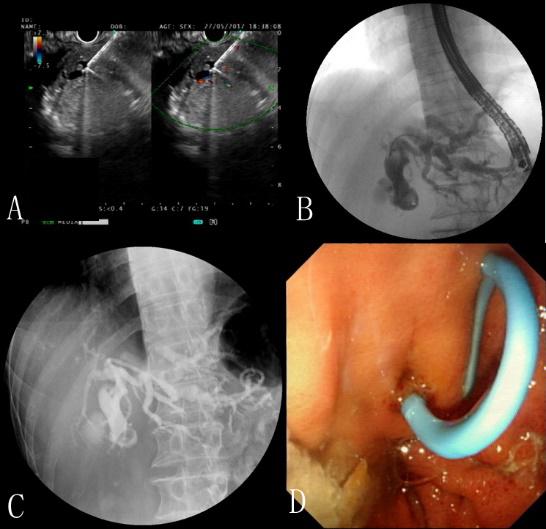

超声内镜引导下胆道引流术治疗恶性梗阻性黄疸

作者:陈萃 孙波 胡冰